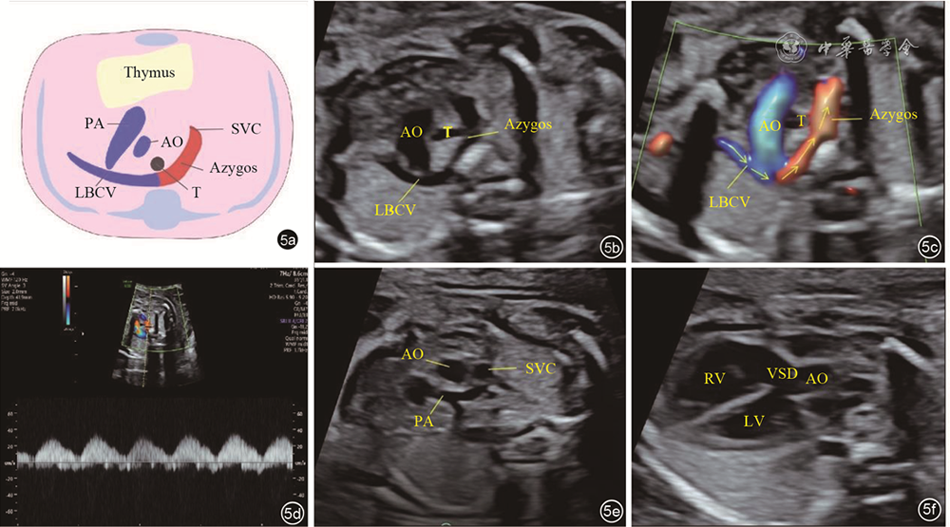

The 43 cases of LBCV abnormalities included the following three types: Abnormal course of the LBCV (traveling under the aortic arch in 25 fetuses, penetrating the thymus in 6, and retroesophageal or retrotracheal LBCV in 2); absent LBCV in 7 fetuses; and abnormal diameter of the LBCV (significantly widened inner diameter in 2 fetuses, and smaller inner diameter in 1). Nineteen were detected with other malformations, including right aortic arch, tetralogy of Fallot, transposition of the great arteries, persistent left superior vena cava, and total anomalous pulmonary vein communication. The mean inner diameter of the LBCV in normal fetuses at 18 to 34 weeks ranged from 1.9 mm to 3.98 mm, which showed a positive linear correlation with gestational age. The regression equation was: LBCV inner diameter (mm)=-0.6796+0.1352× gestational age (GA).

The position, course, and morphology of the LBCV can be observed by prenatal ultrasound. The inner diameter of the normal LBCV increases linearly with gestational age. Knowing the ultrasonographic features and clinical significance of different types of LBCV abnormalities can provide information and evidence for clinical consultation.